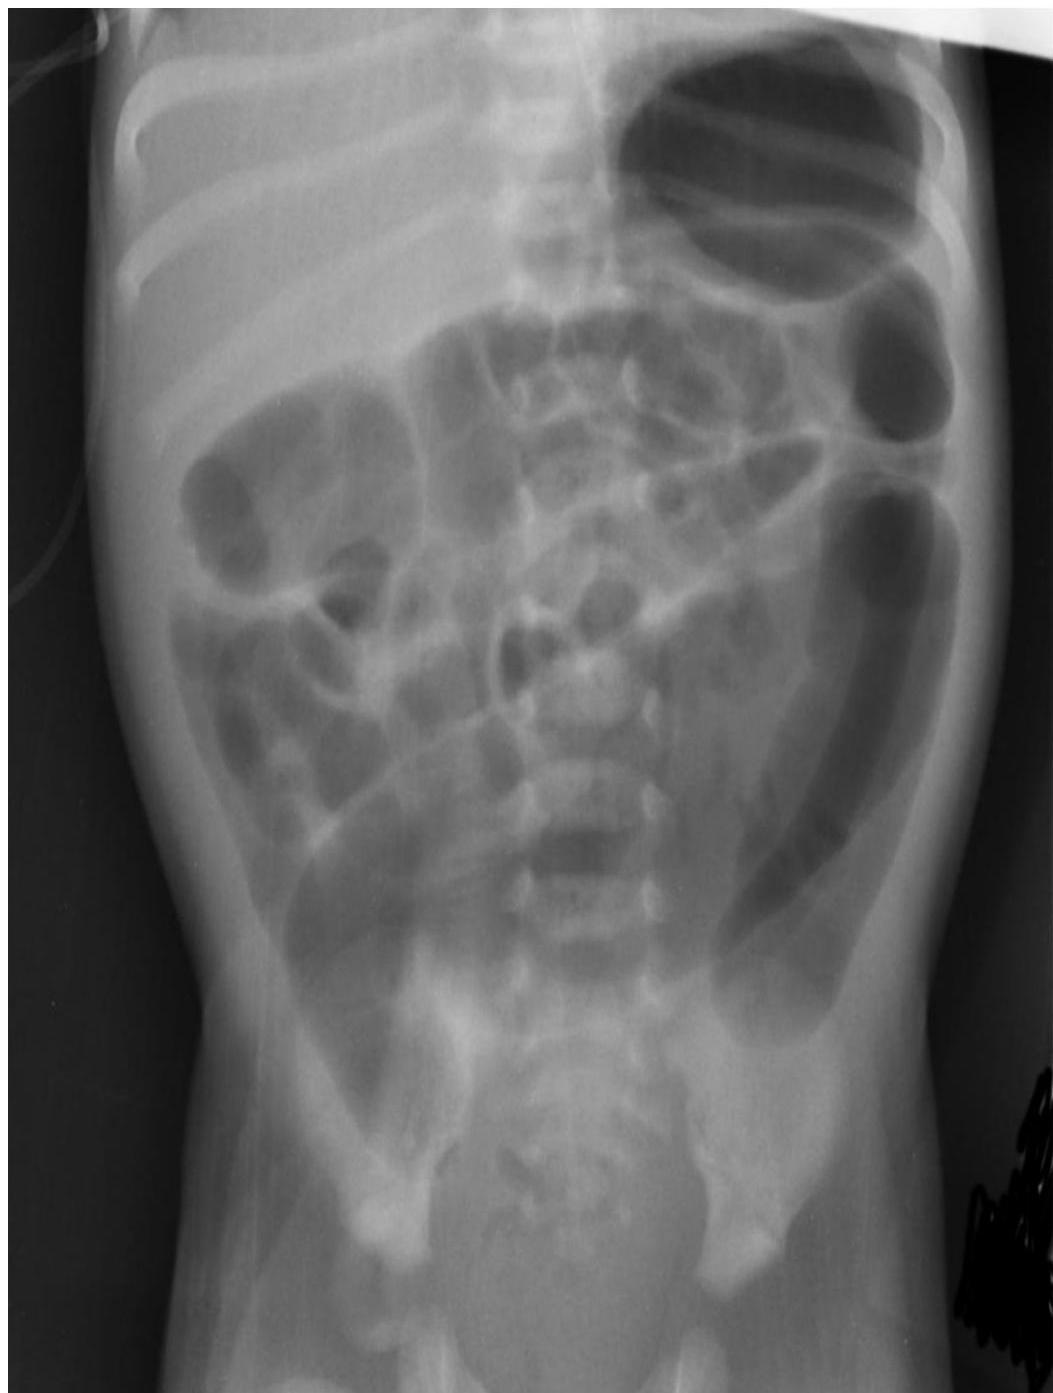

- Erect abdomen X-ray.

- Barium enema: Shows a transitional zone where a market change in caliber occurs, with the dilated normal colon above and the narrowed aganglionic below (should not be done in patient suspected of having enterocolitis → perforation).

- Proximal Dilated Bowel (Normoganglionic)

- Transition Zone (hypoganglionic)

- Contracted Distal Bowel (aganglionic)

The transition zone is in the mid-descending colon.